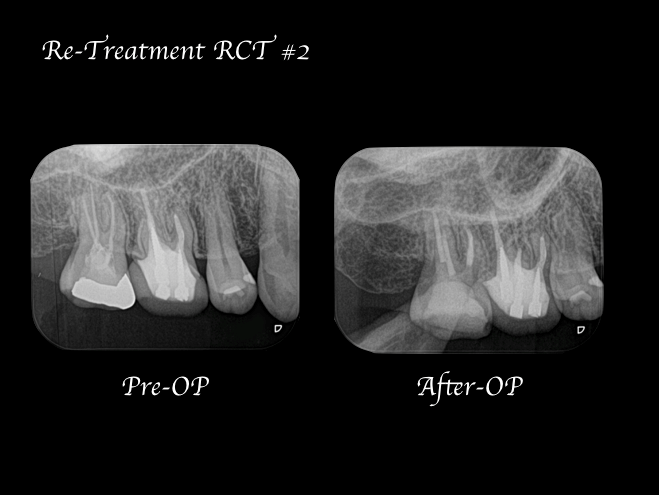

【症例】再根管治療| CT、マイクロスコープを使った精密根管治療

- カテゴリー:再根管治療

| 治療内容 | 再根管治療|精密根管治療 | 期間 | 1週間 |

| 治療回数 | 2回 | 費用 | 154,000円(税込) ※処置当時の料金 |

数週間前より右上がうずく感じがすることを主訴に来院された患者様です。近隣の歯科医院でも相談はしたが、特に問題がないと言い渡され、症状が気になり当院を受診されました。

右上7番には臨床症状(叩くことでの痛み)が確認できるものの、レントゲン上には根尖性歯周炎と判断できる透過像(病変の影)は確認できませんでした。歯科用CTを撮影してみると、近心根と遠心根に明らかな病変を認めました(歯科用CT画像1赤丸)。他の臨床症状と歯科用CT画像から右上7番の根尖性歯周炎と診断しました。

また、同時に近心根には見逃している根管もしくはフィンと言われる極小なスペース(CT画像2赤丸)が存在することも確認できます。

治療中に歯科用顕微鏡(マイクロスコープ)下にてCT画像で確認した部位には手つかずの根管を確認し、処置を行った。

治療回数は2回で終了しています。2回目の治療終了時には初診時で患者様が訴えていた違和感は改善され、次週、問題なければ仮歯の製作に移行する予定。